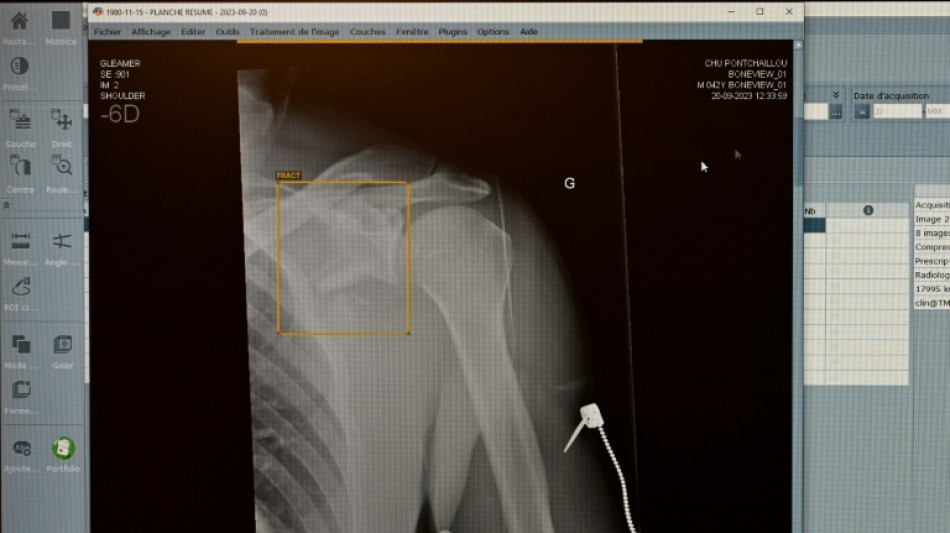

Zweitmeinung von KI bei Gesundheitsproblemen: Für jeden Zweiten vorstellbar / Foto: © AFP/Archiv